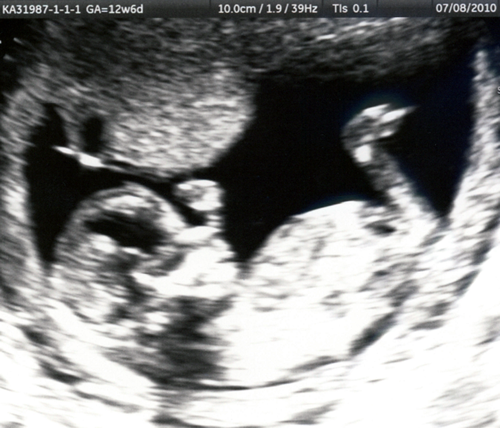

Oh Baby! Here are some of our first photos:

us_1

profle at 13 weeks

us_2

yep, we're having a boy!